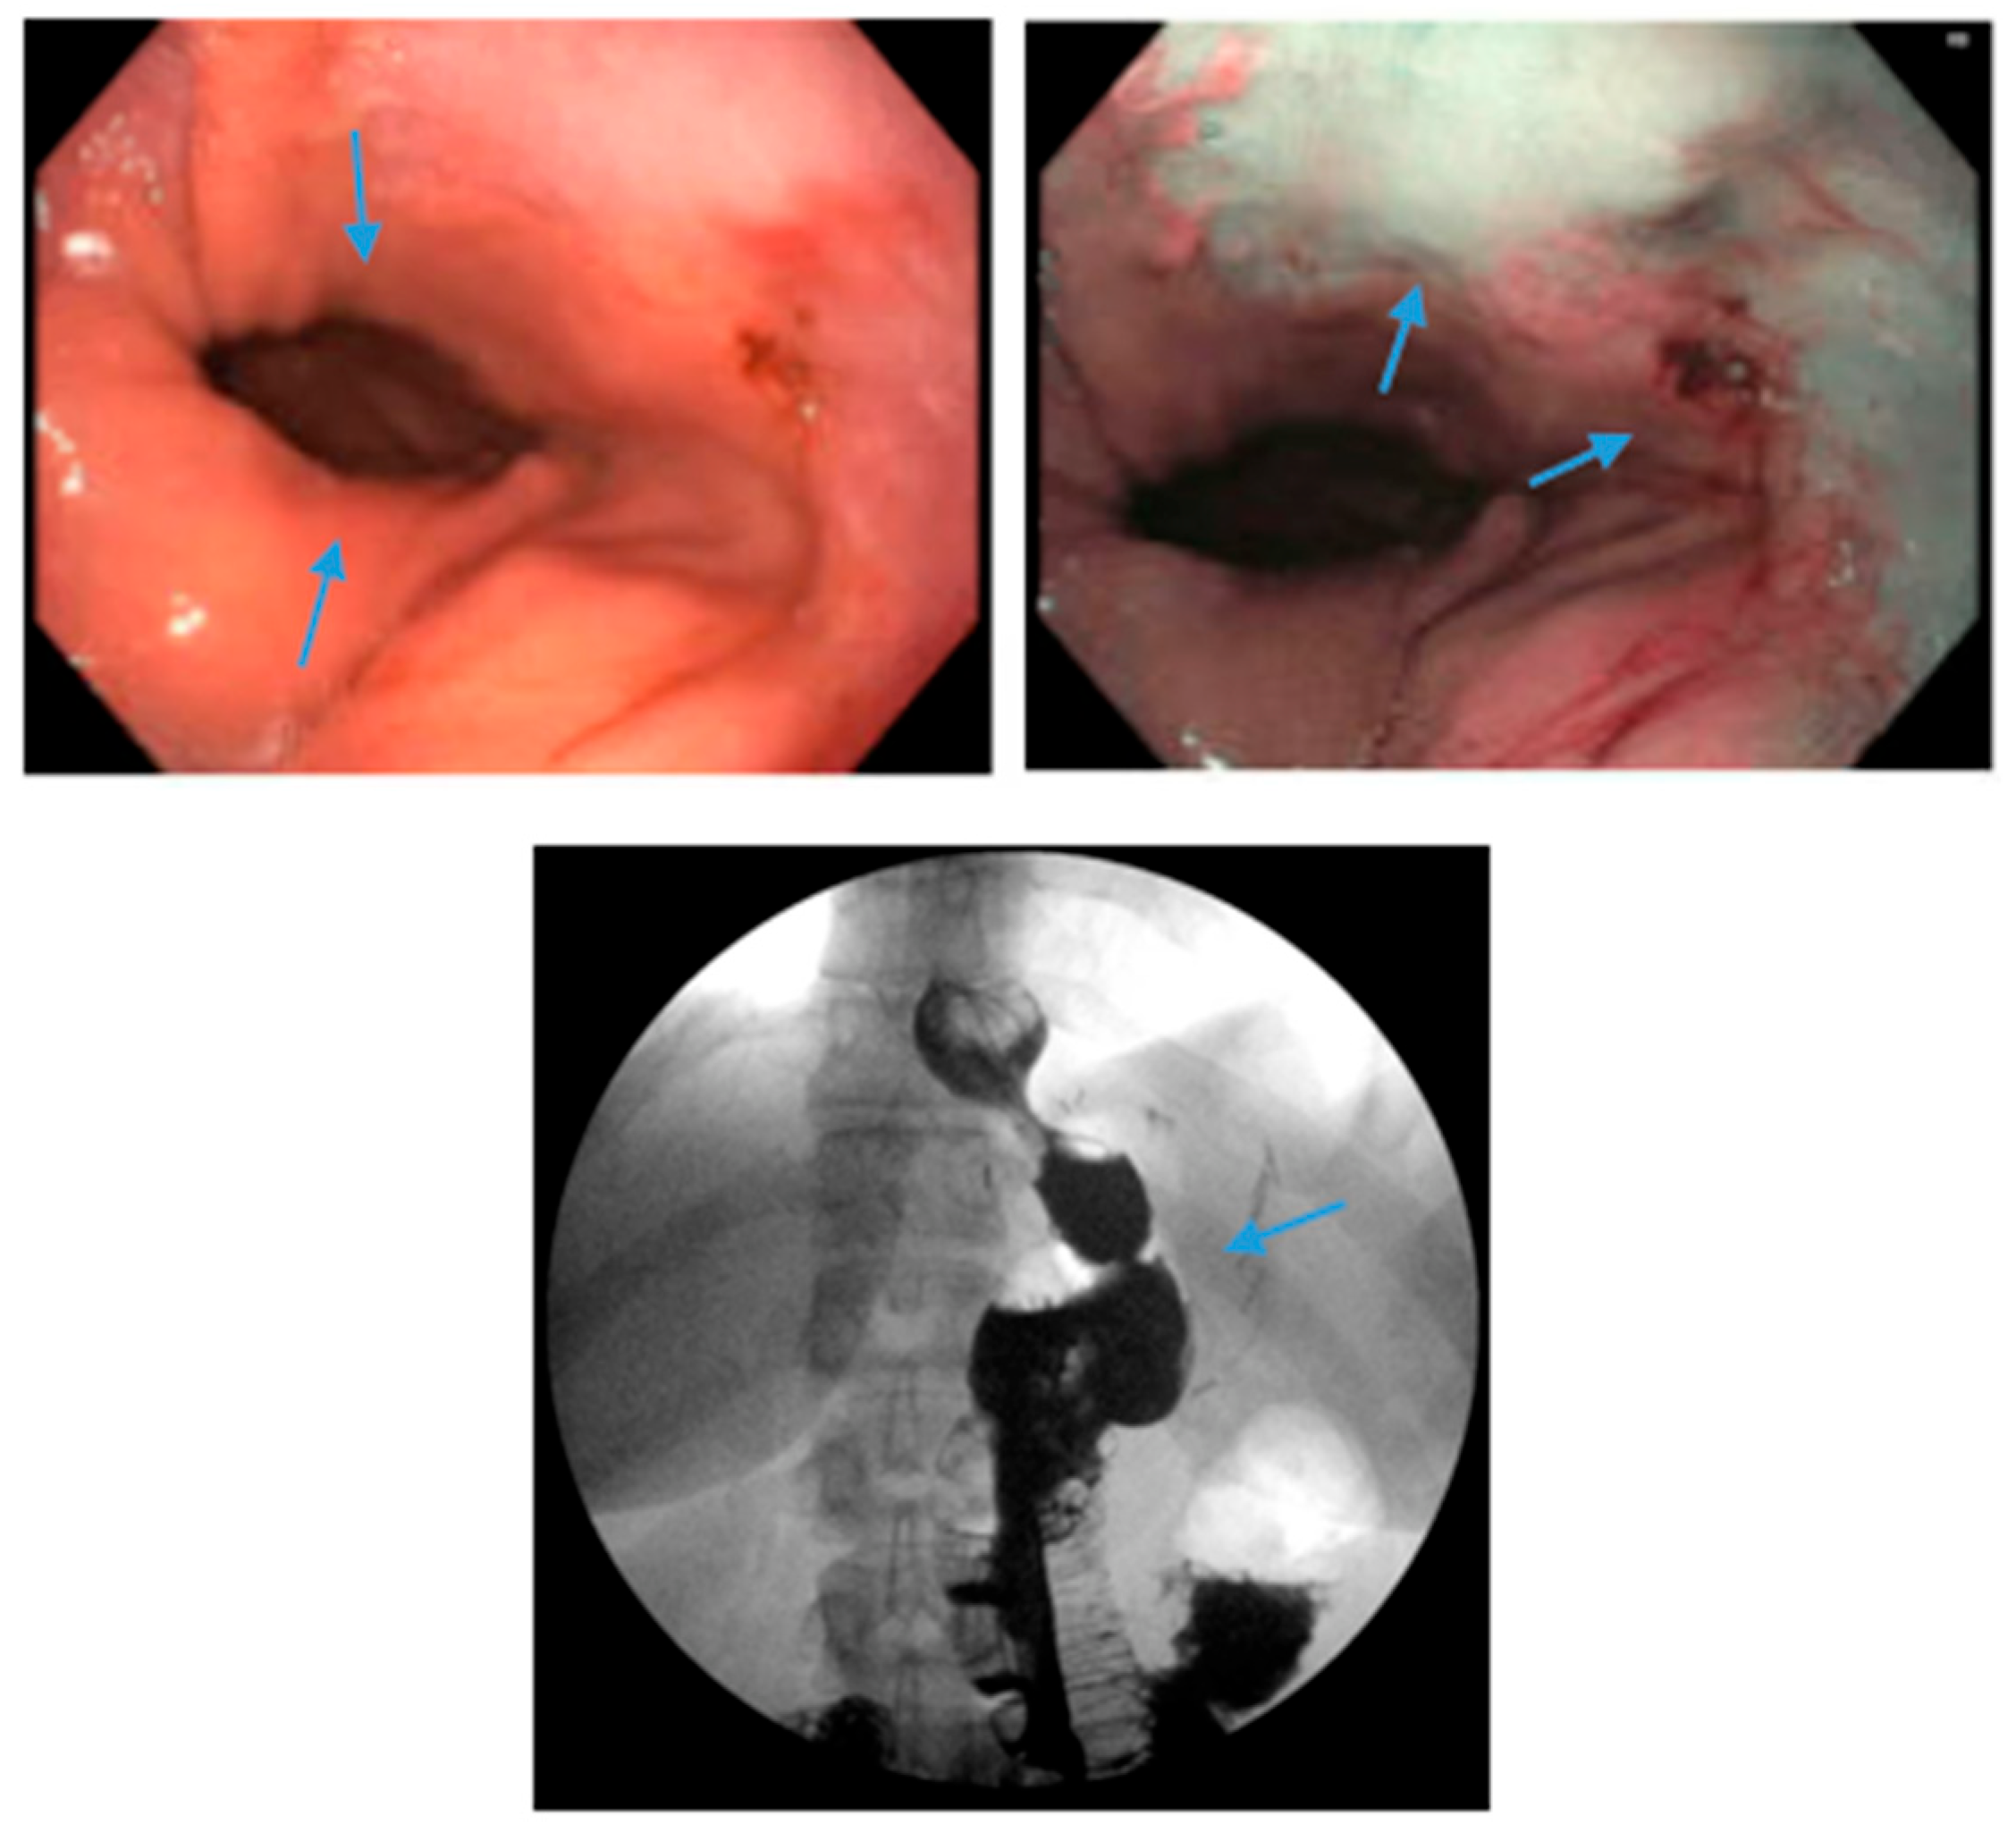

Figure 6.

Endoscopic images reveal a 3 cm hiatal hernia (arrows, top left) and Los Angeles Grade B esophagitis (arrows, top right) in the lower third of the esophagus with narrow-band imaging in a patient post-sleeve gastrectomy with symptoms of gastroesophageal reflux disease. The patient eventually required Roux-en-Y gastric bypass (arrow, bottom) and concomitant hiatal hernia repair, as demonstrated on upper gastrointestinal series.